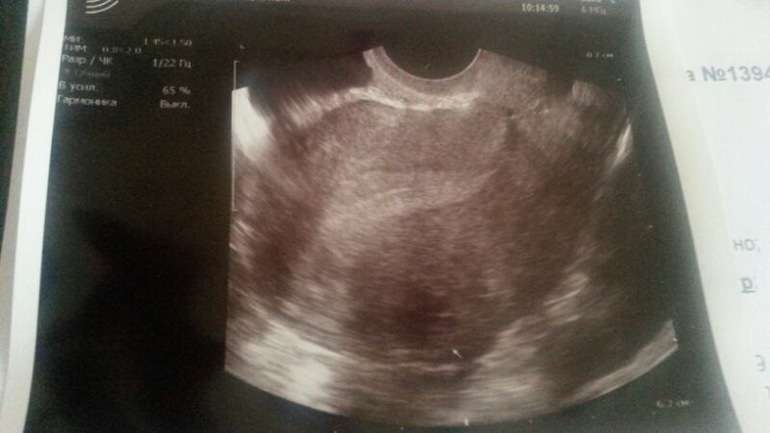

Результаты: УЗИ, КТГ, доплера, скринингабеременность 5 неделя, если это вообще она... полоски на тестах слааабые, задержка неделю.. не выдержало мое сердце ожидания, пошла на УЗИ, нашли кисту, фибромиому, вес что угодно, только не плодное яйцо... вот либо я ни фига не понимаю, либо что, смотрите сами...

Стрелочкой он фибромиому обозначил, а вот вверху справа, маленькое такое, кругленькое... это что??

вверху справа на наружней стенке — сосуд маточный в проекции. Б здесь не видно